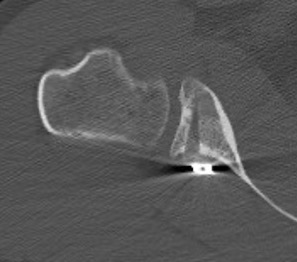

CT

Hill Sachs lesion / posterior bony bankart / glenoid retroversion

Critical posterior glenoid bone loss

- compared successful posterior labral surgery with unsuccessful

- 11% glenoid bone loss - 10 x failure rate

- 15% glenoid bone loss - 25 x failure rate

Glenoid Osteotomy

Indication

Posterior instability with retroversion > 10 degrees / glenoid dysplasia

- osteotomy parallel to articular surface, 1.5 cm from articular surface

- preserves anterior 1 cm of glenoid to prevent iatrogenic fractures